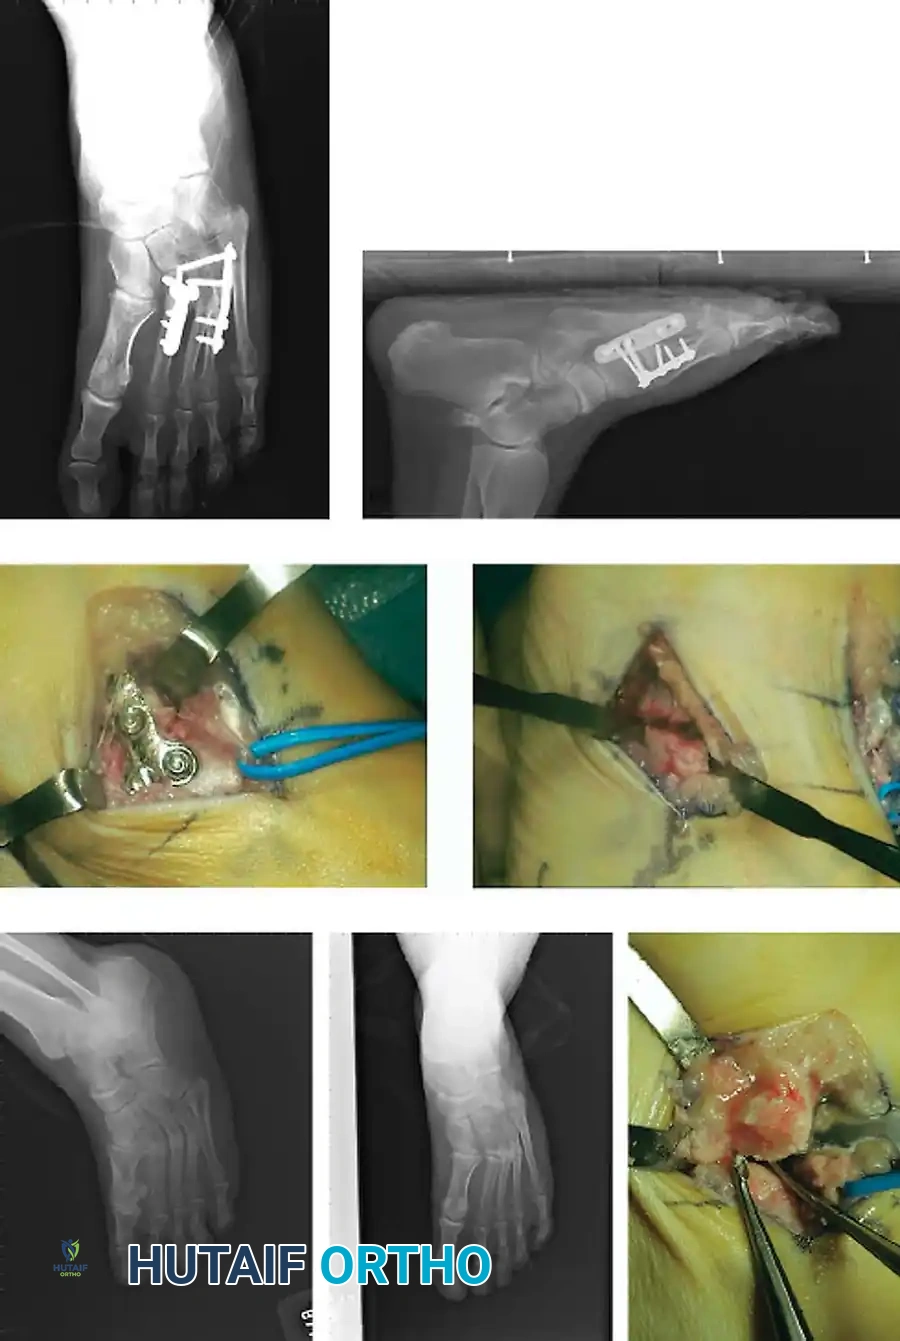

Fig. 86-44, cont’d D-F, After screw fi xation.

Fig. 86-44 D-F. Postoperative radiographs following precise open reduction and internal screw fixation, restoring the articular surface.